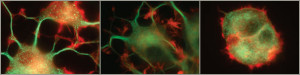

Lo studio, condotto prima su modello animale e successivamente su tre pazienti con glaucoma avanzato, fornisce le prime evidenze che il Fattore di Crescita Nervoso, scoperto negli anni cinquanta dal Premio Nobel Levi Montalcini, somministrato in gocce sulla superficie oculare, previene i danni e migliora la funzione della retina e del nervo ottico provocati dal glaucoma. La sperimentazione effettuata sui tre pazienti ha mostrato miglioramenti duraturi delle funzioni del nervo ottico, con potenziamento del campo visivo e della vista.

Per arrivare tuttavia all’applicazione clinica del nuovo collirio saranno ancora necessarie: la produzione di rhNGF (Fattore di Crescita Nervoso sintetico), la sua approvazione e una sperimentazione clinica su un ampio campione di pazienti per confermare i risultati dello studio pilota. Il Fattore di Crescita Nervoso e’ una neurotrofina espressa fisiologicamente in diversi tessuti del corpo umano. Ha effetti protettivi e rigenerativi sui neuroni del sistema nervoso centrale e periferico.